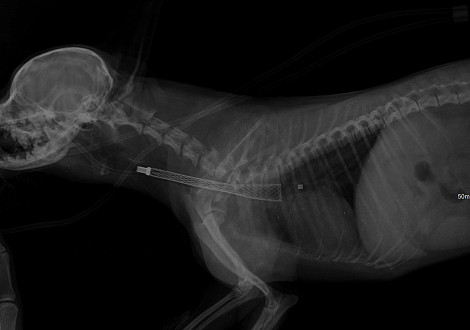

Процесс стентирования проводится под эндоскопическим и радиологическим контролем и занимает 10–20 минут. В зависимости от тяжести состояния, в котором был доставлен пациент в клинику, он остается в стационаре от 1 до 2 суток. Первые 14 дней животное получает стандартную схему антибиотиков, противокашлевые препараты, муколитические средства, а в некоторых случаях – стероиды. Приблизительно через 21 день нитиноловая сетка заполняется прорастающим эпителием трахеи, и стент полностью фиксируется в трахее.

По состоянию животного проводятся контрольные рентгенологические обследования через 4 недели. Далее — 1 раз в 6 месяцев.

Рентегнологическая картина коллапса трахеи

Нитиноловый стент DEXTRONIX после установки